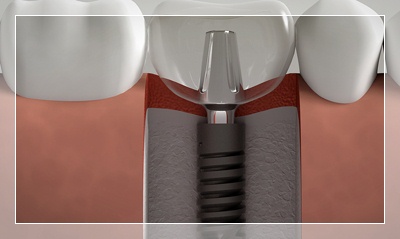

Dental implantlar resimlerde de görebileceğiniz üzere, diş kaybının yaşandığı bölgelerde çene kemiği içine açılan yuvalara yerleştirilirler. Uygun koşullar oluştuğunda, yani kısaca implant vücudunuza sıkıca tutunduğunda (osseointegrasyon), üst yapı hazırlanarak protez tamamlanır. Doğru planlama, doğru cerrahi teknik ve kaliteli malzemeyle uygulanan implantların, günlük bakımı ve periyodik kontrolleri de gerektiği gibi yapılırsa uzun yıllar boyunca hizmet vermesi mümkündür.